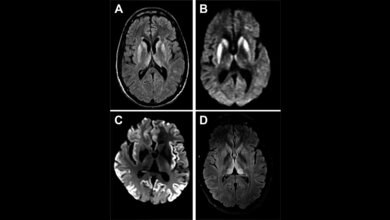

Mithilfe von In-vitro- und Zellkultur-Ansätzen, Tiermodellen und Gehirnproben von Patienten mit der Creutzfeldt-Jakob-Erkrankung konnten die Forschenden zeigen, dass fehlgefaltete Prion-Proteine die Verklumpung und Inaktivierung von TDP-43 auslösen können. Die Prion-Proteine interagieren in vitro und in Zellen mit TDP-43 und induzieren dadurch die Bildung von TDP-Aggregaten in der Zelle. Infolgedessen ist die TDP-43-abhängige Spleißaktivität im Zellkern deutlich verringert, was zu einer veränderten Proteinexpression führt. „Prion-Protein und TDP-43 sind sozusagen ‚partners in crime‘ bei neurodegenerativen Erkrankungen“, so Jörg Tatzelt.

Eine Analyse von Gehirnproben zeigte, dass bei einigen Creutzfeld-Jacob-Patienten neben den Prion-Protein-Ablagerungen auch TDP-43-Aggregate zu finden waren. Diese Studie hat einen neuen Mechanismus aufgezeigt, wie krankheitsaassoziierte Prion-Proteine physiologische Signalwege durch Cross Seeding beeinträchtigen können.